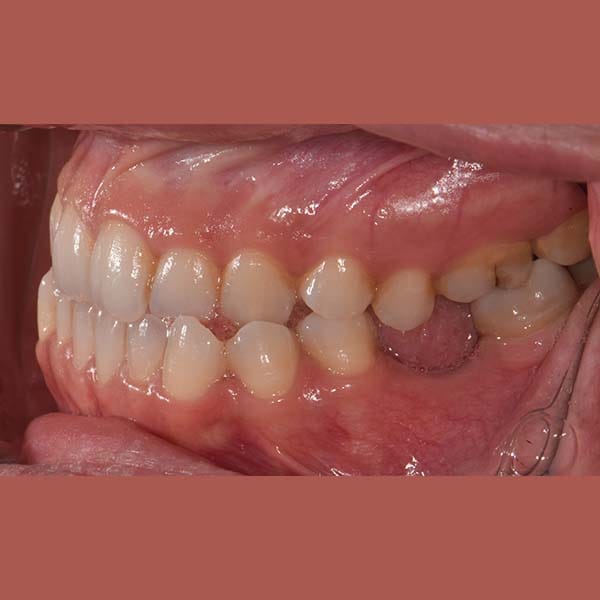

عانت هذه الشابة من بروز واضح في الذقن ناتج عن تقدم الفك السفلي، مما أثر على تناسق وجهها وسبب لها عضة معكوسة أمامية.

كما تظهر الصور، كانت النتيجة تحولاً كاملاً. تم استعادة الشكل الطبيعي للذقن والفك السفلي، وتم تصحيح العضة المعكوسة. في النهاية، أصبح بإمكان مراجعتنا الشابة أن تستمتع بابتسامة مميزة وواثقة وملامح وجه متناغمة.